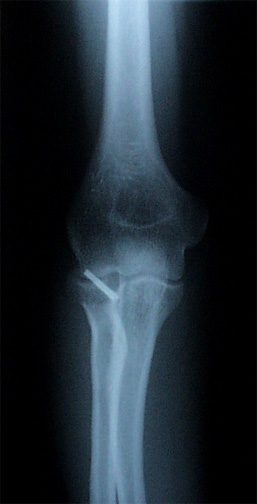

Straight Elbow I was awake during my elbow surgery, which was weird since I could hear Dr. Howson and her assistant debating about what size of screw to use, worrying about the pins slipping, and tapping at things with what sounded like a little hammer. (The pins were plastic and will disintegrate, but the screw will be with me forever.)